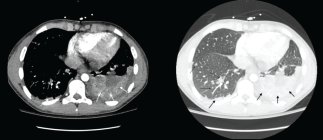

Acute osteomyelitis (AOM) is defined as an inflammation of the bone secondary to infection. Among the most common complications of AOM is the development of a periosteal abscess and the extension of the focus locally to muscle (pyomyositis) and/or joint (osteoarthritis). However, complications with much lower incidence have been described, including deep vein thrombosis (DVT) and septic pulmonary embolisms (SPE), mainly associated with S. aureus infections. The AOM + DVT + ESP triad is a fairly uncommon entity in the pediatric population; however, if it is not diagnosed and treated in time, it implies a high morbidity and mortality. Treatment, which must be early and aggressive, includes targeted antibiotic therapy, anticoagulation, and focused control surgery. In this article, we describe the case of a 14-year-old boy with disseminated staphylococcal infection associated with the triad AOM+ DVT + SPE.